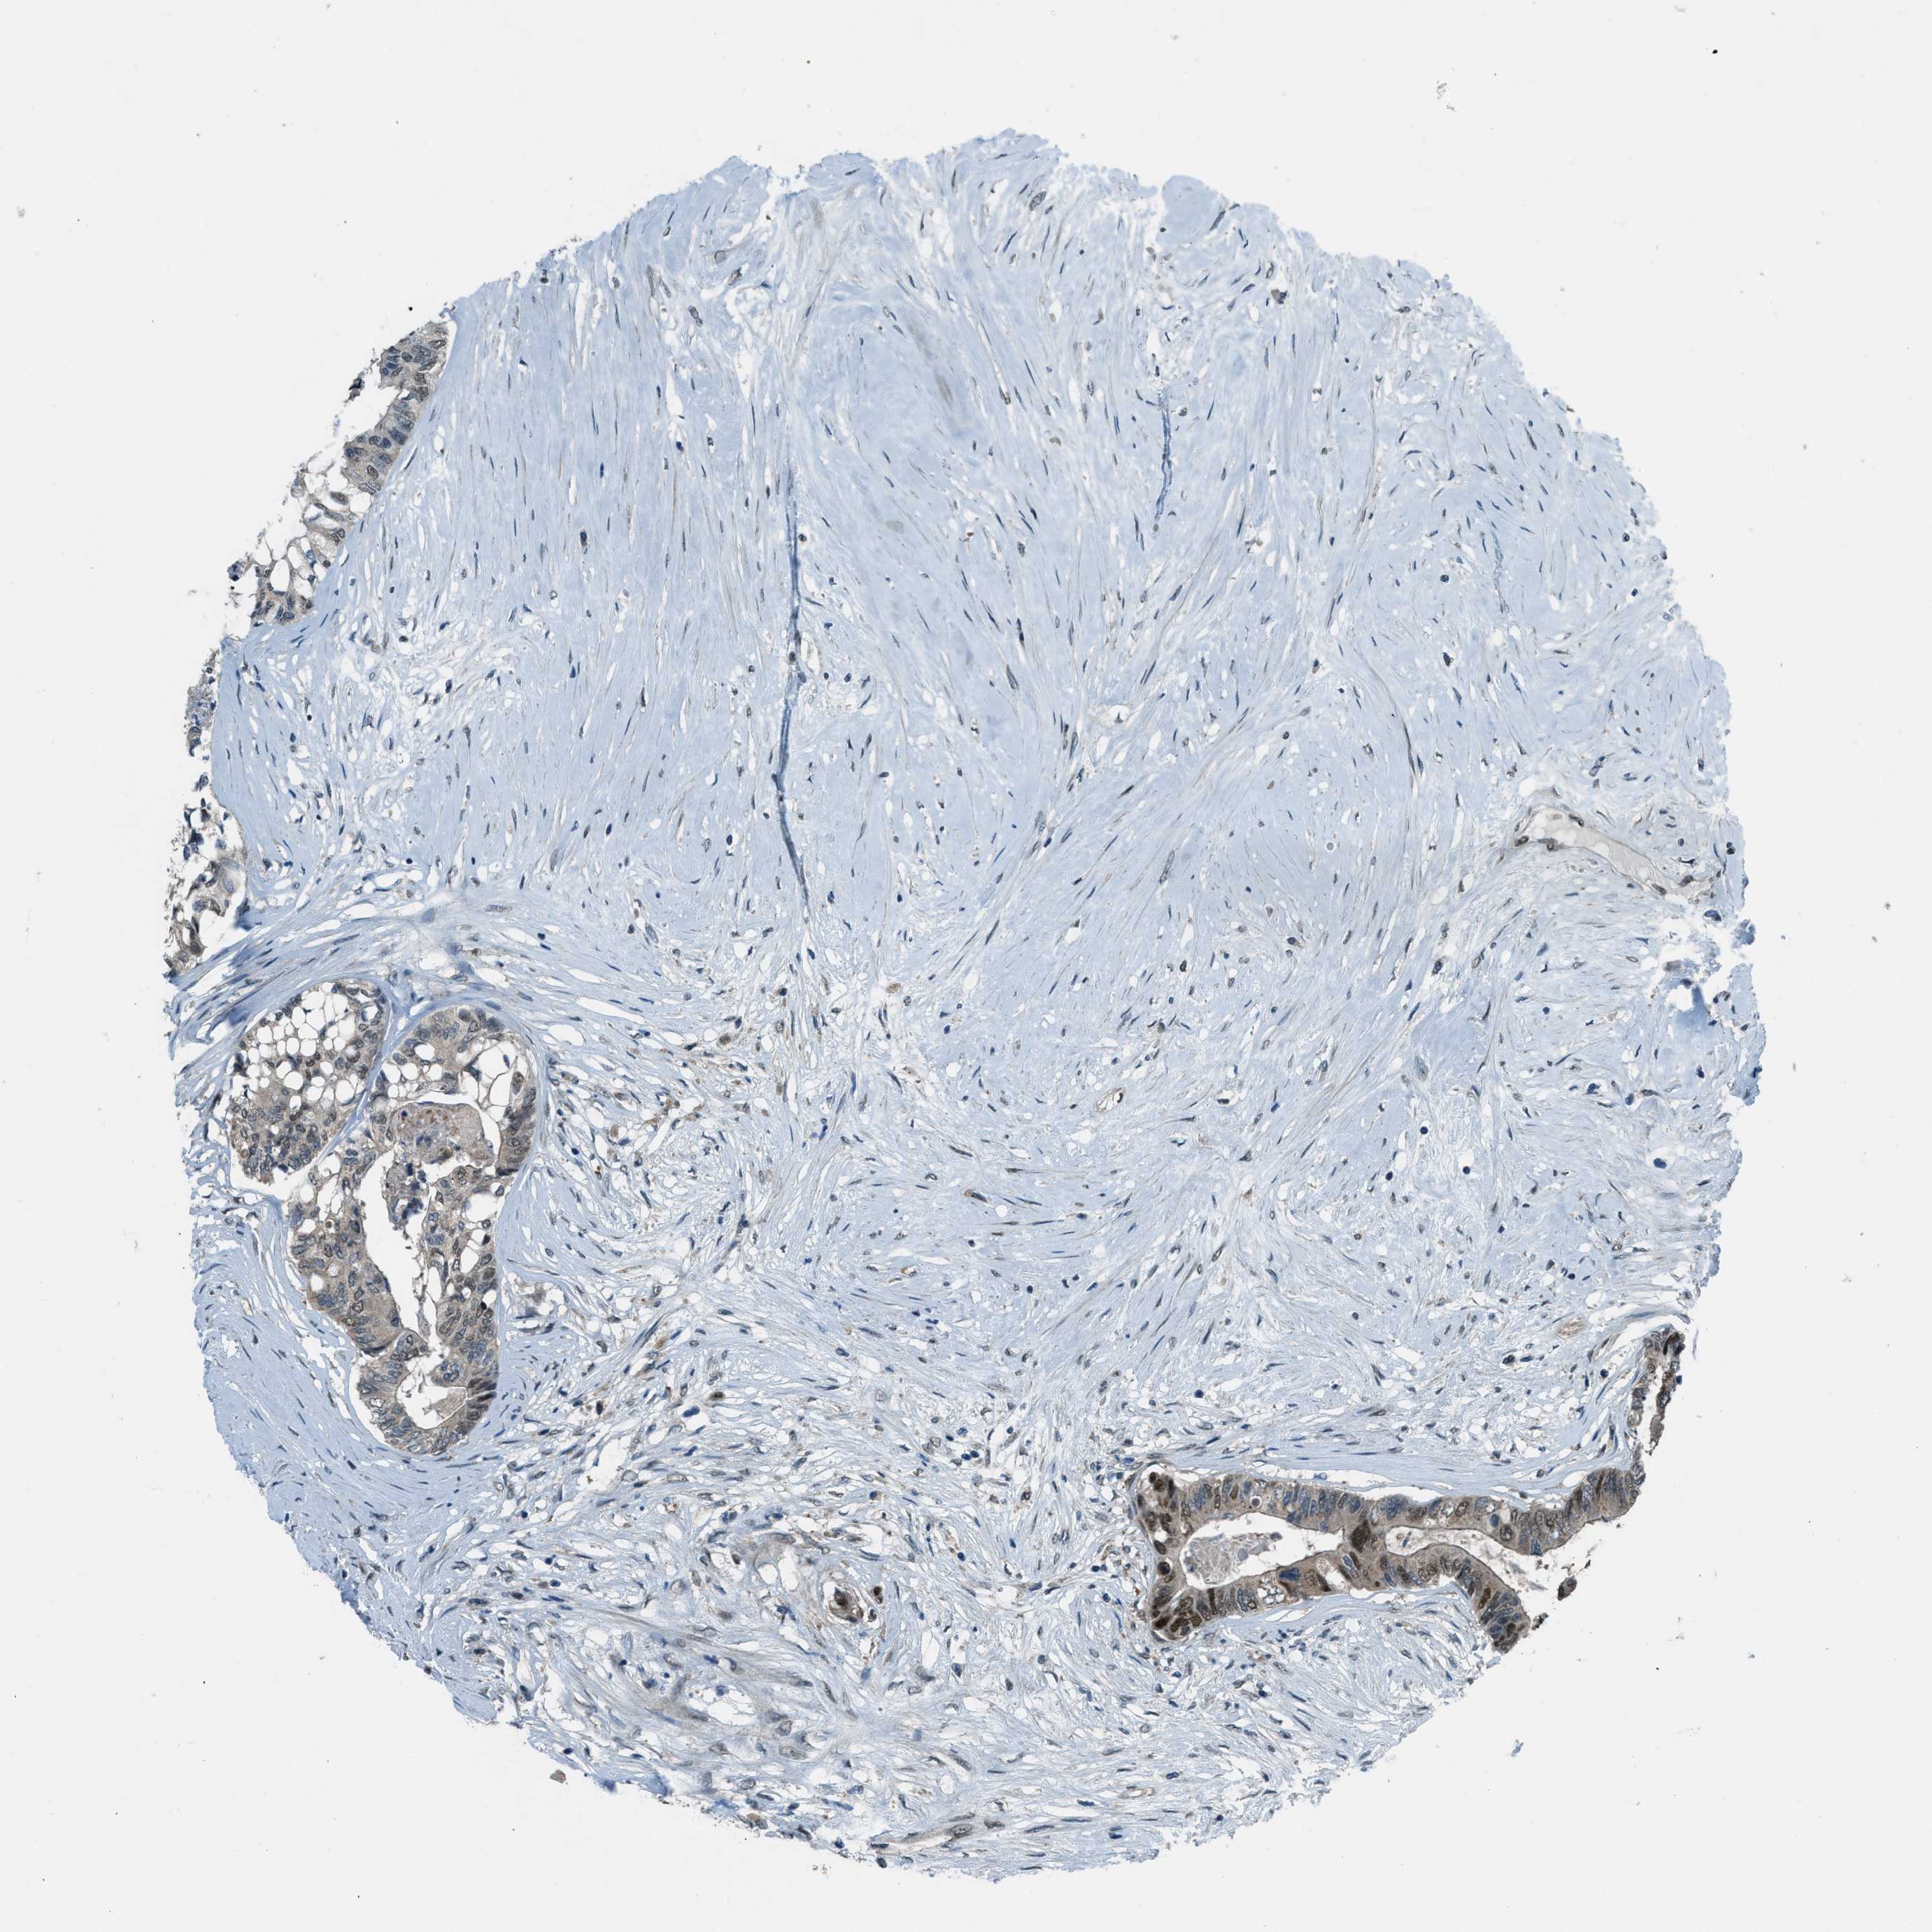

CANCER COLORECTAL CANCER Show tissue menu

Colorectal cancer

Human cancer

Colon adenocarcinoma